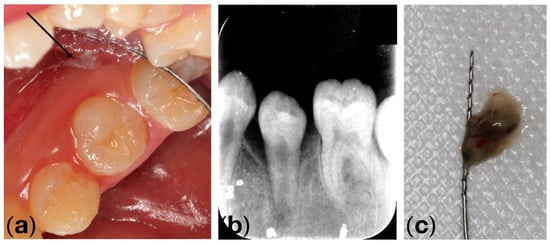

2. Case Report

2.2. Clinical Exams and Diagnosis

2.3. Therapeutic Plan

3. Results